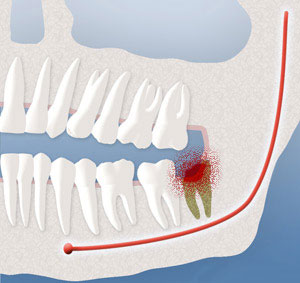

After Extraction of Wisdom Teeth

In most cases, the removal of wisdom teeth is performed under IV sedation or general anesthesia. Through the use of our Ambulatory Surgery Center (ASC) we can also provide inhalational anesthetics to help sedate you before placement of an IV catheter. These options, as well as the surgical risks (i.e. sensory nerve damage, sinus complications), will be discussed with you before the procedure is performed. Once the teeth are removed, the gum is often sutured. To help control bleeding, bite down on the gauze placed in your mouth. You will rest under our supervision in the office until you are ready to be taken home. Upon discharge, your postoperative kit will include postoperative instructions, usually a prescription for pain medication, antibiotics, and a follow-up discussion in about one week. If you have any questions, please do not hesitate to call us at Olympia Office Phone Number360-456-5678.

A primary concern is a nerve within the lower jaw bone that supplies feeling to the lower lip, chin, and tongue. This nerve is frequently very close to the roots of the lower wisdom teeth. Having these teeth out between the ages of 12 and 18 usually provides shorter roots so that the nerve is not so close to the roots of these teeth. Occasionally, when the teeth are removed, and especially in older patients, the nerve can become injured. When local anesthesia wears off, you may experience a tingling or numbing sensation in the lower lip, chin, or tongue. Should this occur, it is usually temporary and will resolve gradually over a period of weeks or months. On rare occasions it can result in a permanent alteration of sensation similar to having local anesthesia. We feel that you should be aware of this possibility before consenting to surgery.